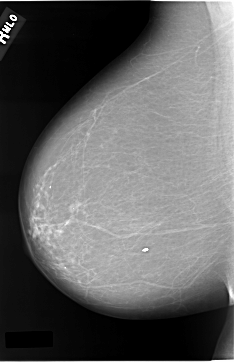

C_0037_1.LEFT_CC

LEFT_MLO LINES 5816 PIXELS_PER_LINE 3824 BITS_PER_PIXEL 12 RESOLUTION 50 OVERLAY